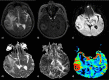

The role of conventional Magnetic Resonance Imaging (MRI) in the detection of cerebral tumors has been well established. However its excellent soft tissue visualization and variety of imaging sequences are in many cases non-specific for the assessment of brain tumor grading. Hence, advanced MRI techniques, like Diffusion-Weighted Imaging (DWI), Diffusion Tensor Imaging (DTI) and Dynamic-Susceptibility Contrast Imaging (DSCI), which are based on different contrast principles, have been used in the clinical routine to improve diagnostic accuracy. The variety of quantitative information derived from these techniques provides significant structural and functional information in a cellular level, highlighting aspects of the underlying brain pathophysiology. The present work, reviews physical principles and recent results obtained using DWI/DTI and DSCI, in tumor characterization and grading of the most common cerebral neoplasms, and discusses how the available MR quantitative data can be utilized through advanced methods of analysis, in order to optimize clinical decision making.